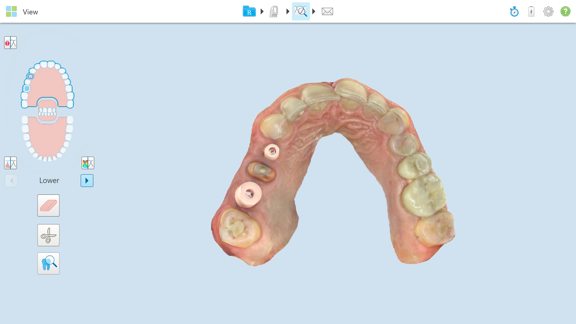

4. Impressions for the Final Restoration

Once the implant has fully integrated with the bone, we take impressions for your final restoration. This step typically occurs about two to three months after the initial implant placement.